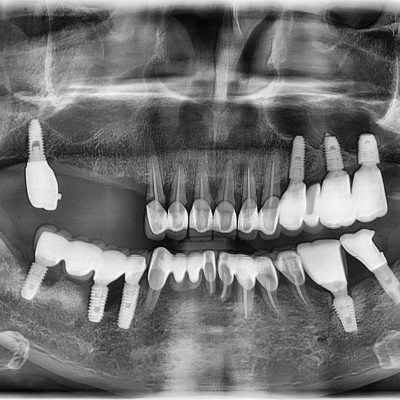

임플란트 재수술

임플란트 재수술 #14.15.16.17 타원 임플란트 제거 후 임플란트 식립+ 치조골 이식술 시행하였습니다.

작성자 이턱이 작성일 01-27 조회 111